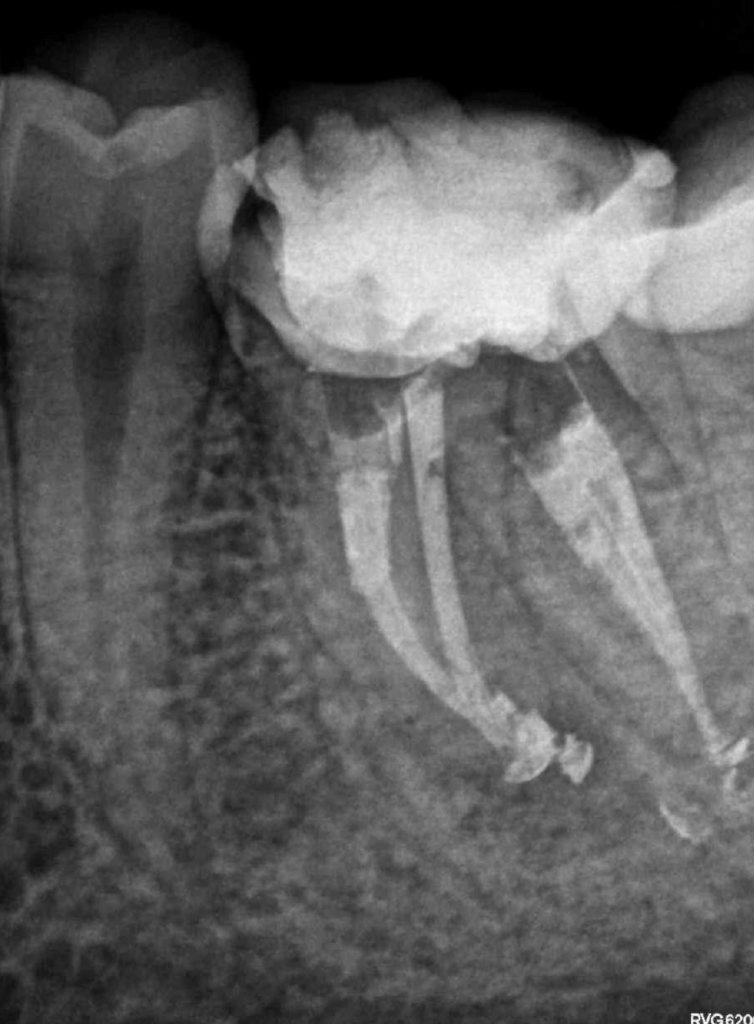

Reco preendo + 4 conductos molar superior

Molar superior

Retratamiento Molar Superior

Retratamiento Primer Molar Superior